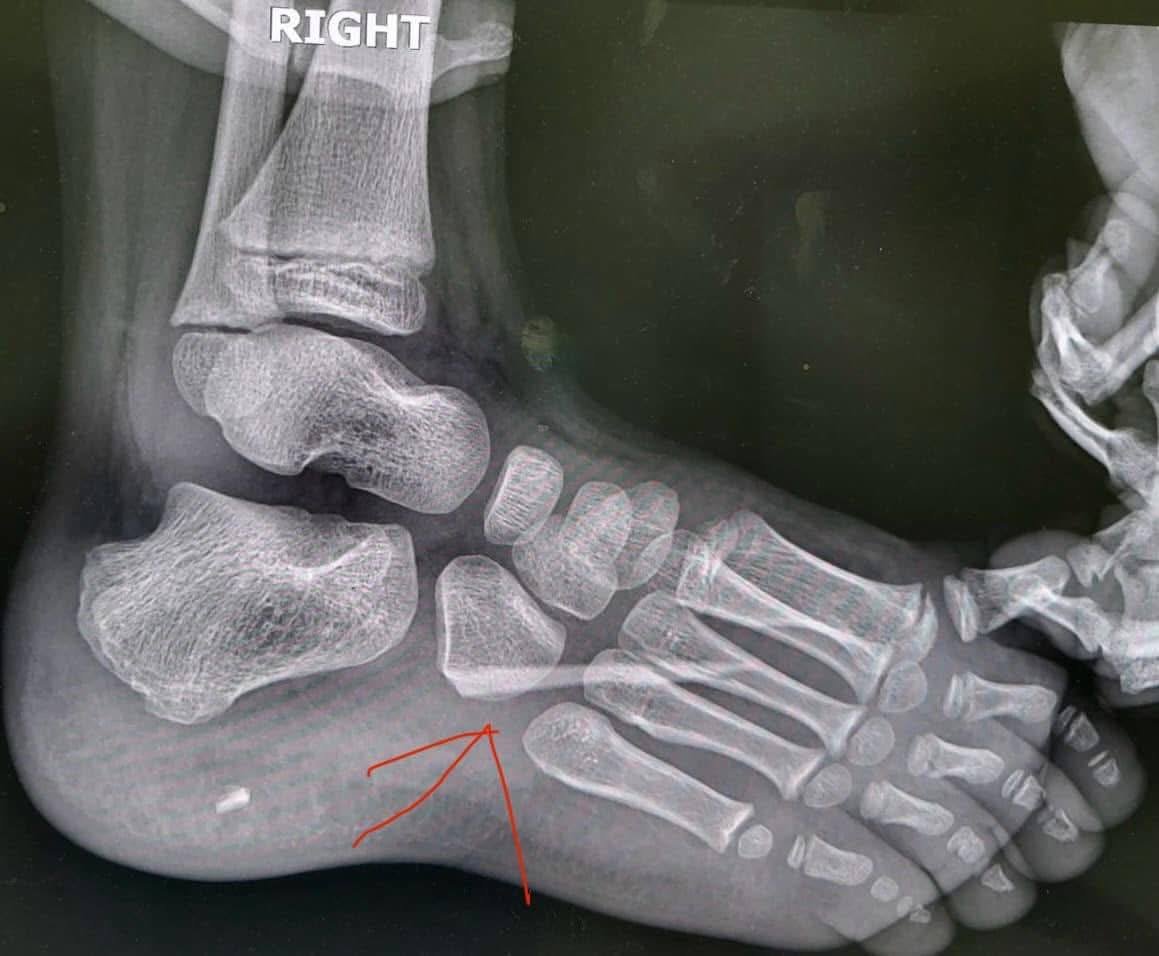

Після клінічного огляду та термінового рентгенологічного обстеження медики зіткнулися з несподіваною та шокуючою знахідкою: у глибині стопи було виявлено велике стороннє тіло – гострий уламок скла.

Вінниченко, що знаходився у стопі, міг спровокувати серйозне запалення, пошкодження сухожиль чи нервів.